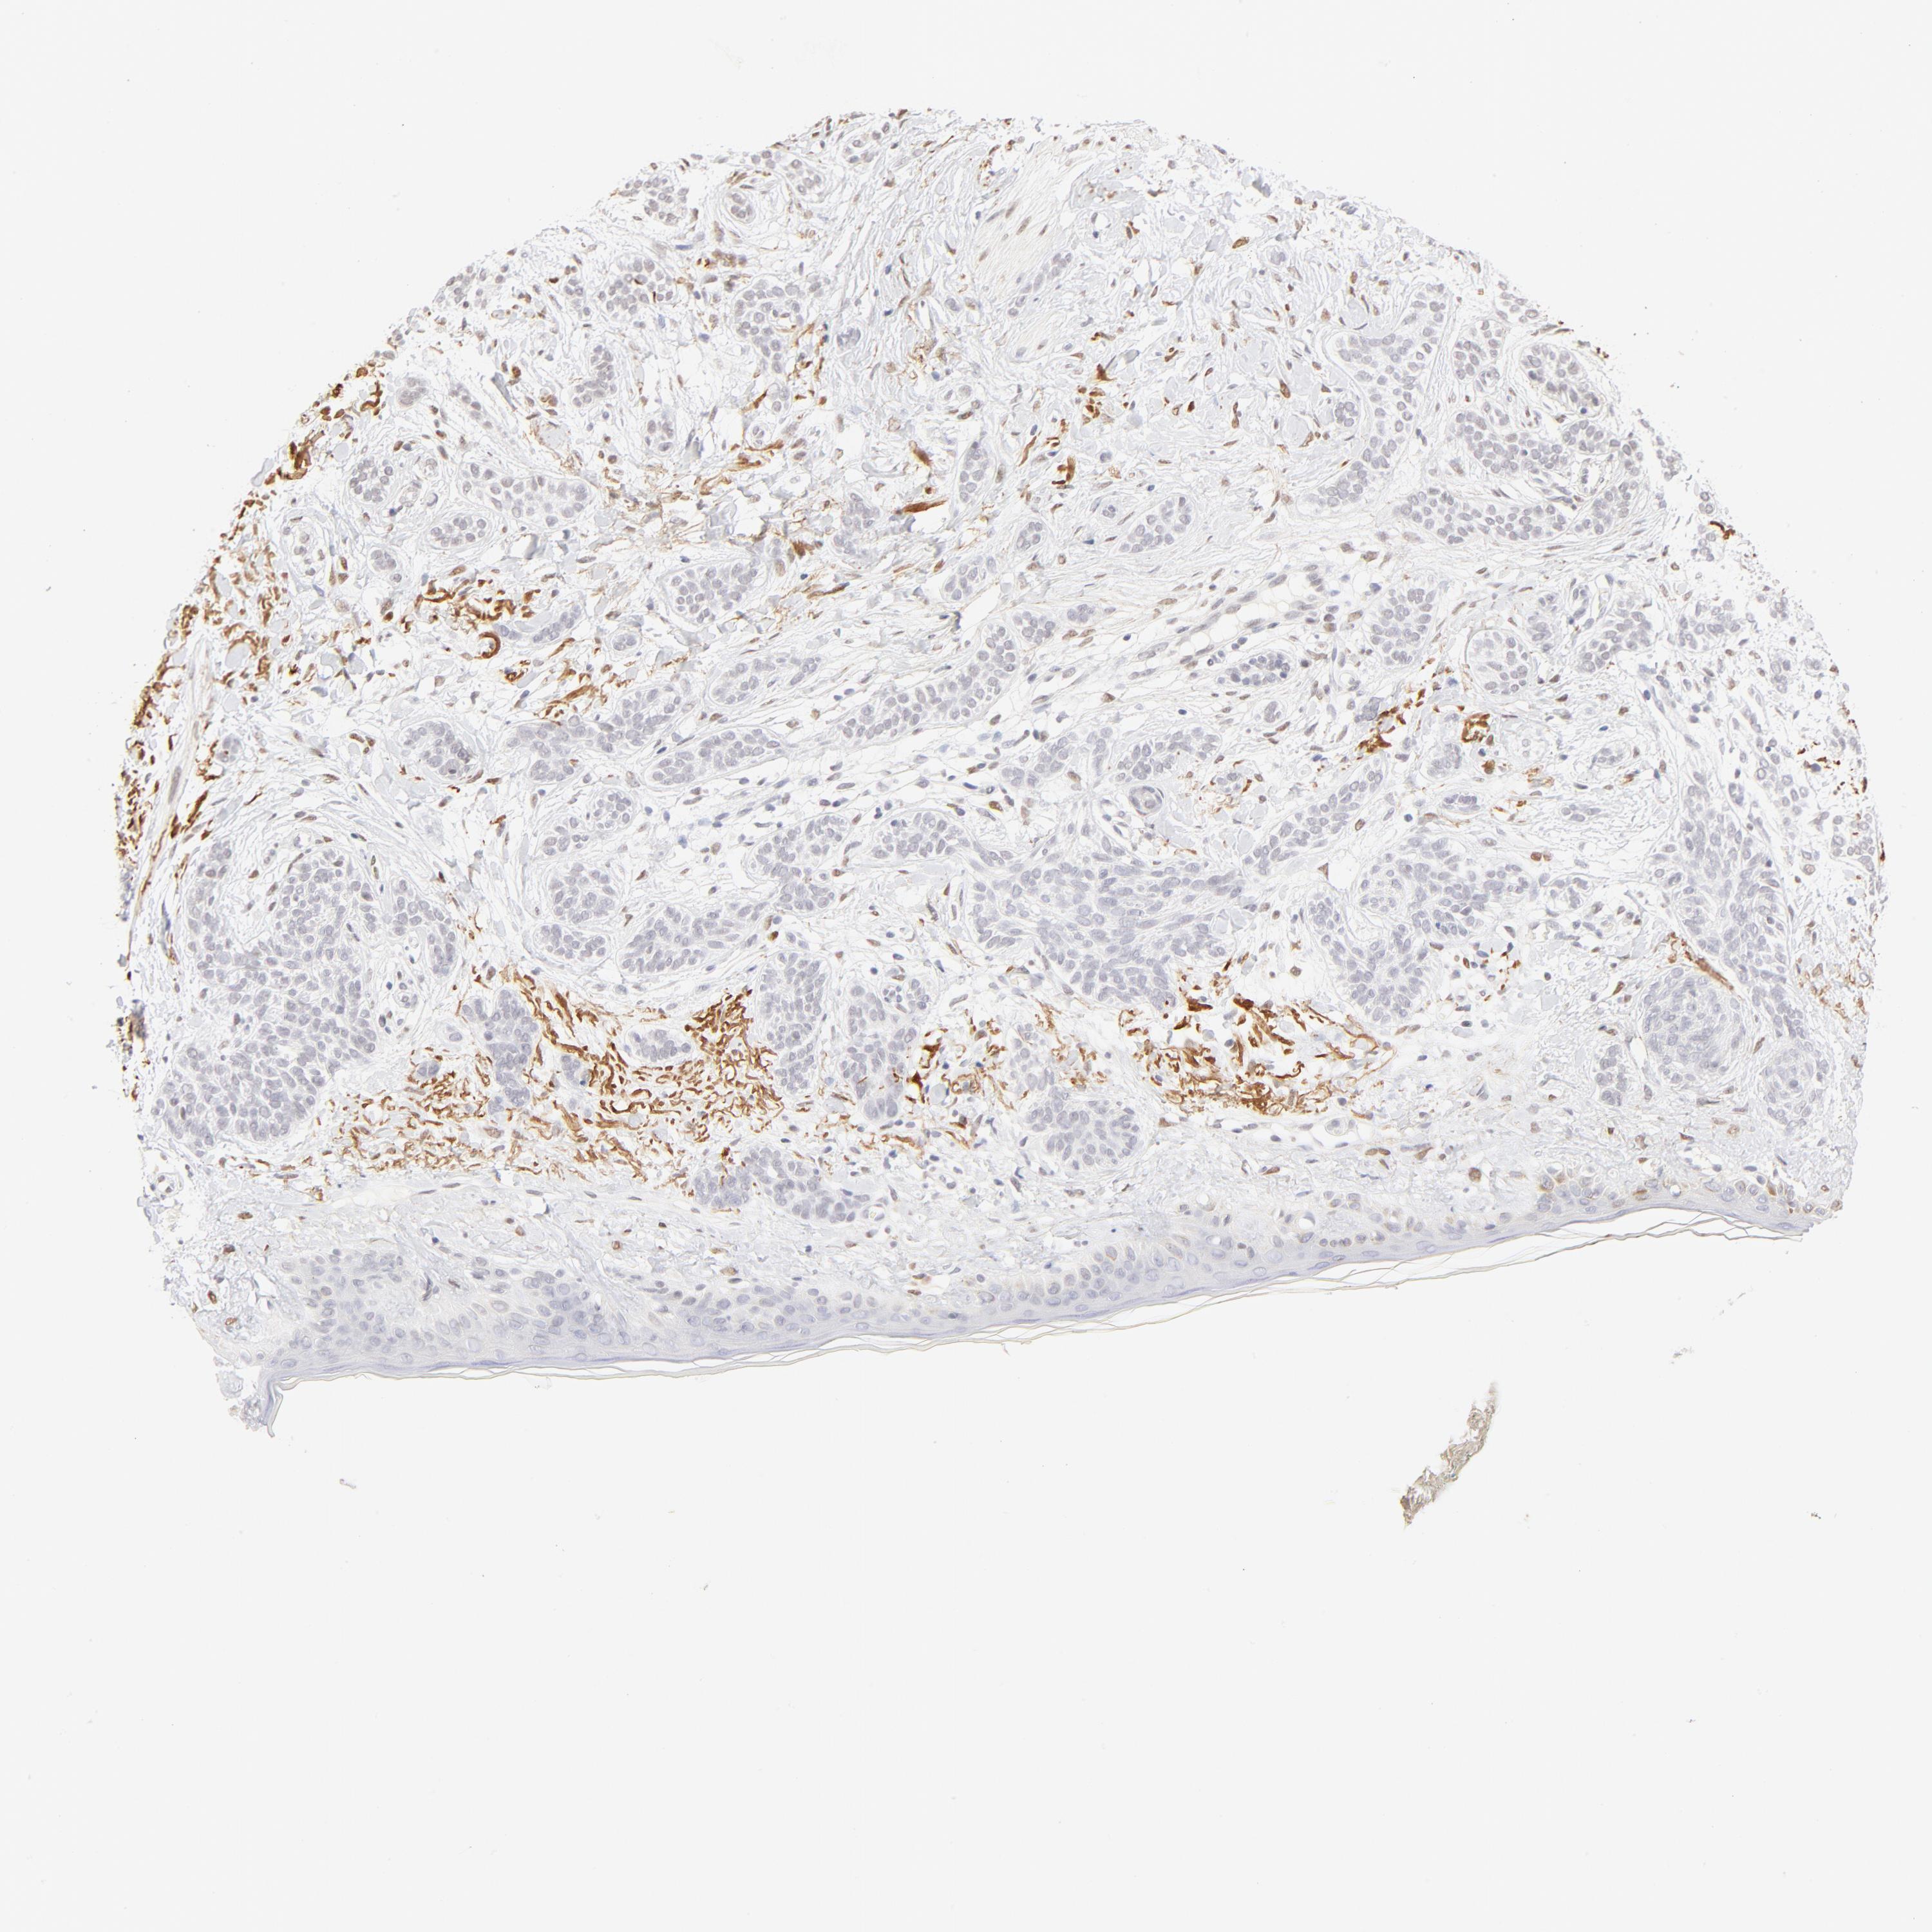

SKIN CANCER - Protein expressioni

A mouse-over function shows sample information and annotation data. Click on an image to view it in a full screen mode. Samples can be filtered based on level of antibody staining by selecting one or several of the following categories: high, medium, low and not detected. The assay and annotation is described here.

Each image is clickable and will lead to virtual microscopy that enables deeper exploration of all samples and also displays staining intensity scores, fraction scores and subcellular localization as well as patient and tissue information for each sample.

Antibody HPA003505

Staining

High

Medium

Low

Not detected

Intensity

Strong

Moderate

Weak

Negative

Quantity

>75%

75%-25%

<25%

None

Location

Nuclear

Cytoplasmic/membranous

Cytoplasmic/membranous,nuclear

Squamous cell carcinoma, NOS